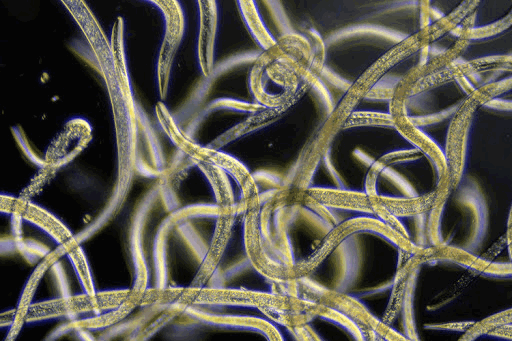

Для диагностики трипаносомоза используется световая микроскопия крови (тонкий или толстый мазок) или пунктата лимфоузла. Концентрация трипаносом в крови часто низкая, поэтому различные концентрационные методики увеличивают чувствительность диагностических методов. Серологической обследование часто неинформативно.

Световая микроскопия крови (тонкий или толстый мазок) или образца другой жидкости

Диагноз африканский трипаносомиаз ставится по идентификации трипаносомы в пробе из шанкра, лимфоузла, крови, биопсии костного мозга или, во время поздней стадии инфекции– цереброспинальной жидкости (ЦСЖ). Предпочтительным источником являются мазки крови для T. b. rhodesiense и жидкость из увеличенного лимфатического узла для T. b. gambiense. Влажные препараты должны быть исследованы на подвижные трипаносомы, мазки должны быть зафиксированы, окрашены по методу Гимза (или Филд) и исследованы. Концентрация трипаносом в крови часто низкая, поэтому различные концентрационные методики (например, центрифугирование, миниатюрное анионообменное центрифугирование, количественное исследование лейкоцитарной пленки в центрифугате крови) увеличивают чувствительность диагностических методов.